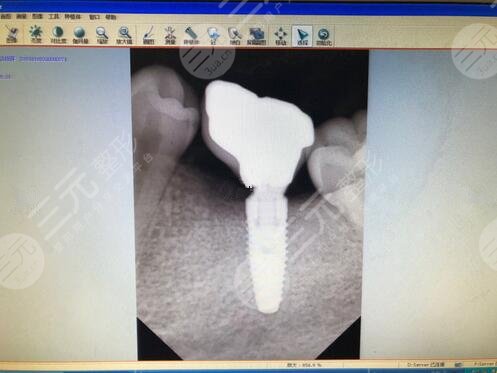

在手术之前,医生让我拍了一张片,看了这张片后,医生说我牙龈的骨量太少,建议我做内提。了解原因后才知道,由于我拔完牙之后隔了两年才来种牙,期间越拖越久导致我的骨量越来越少。所以大家种牙一定要及时,不要像我这样。